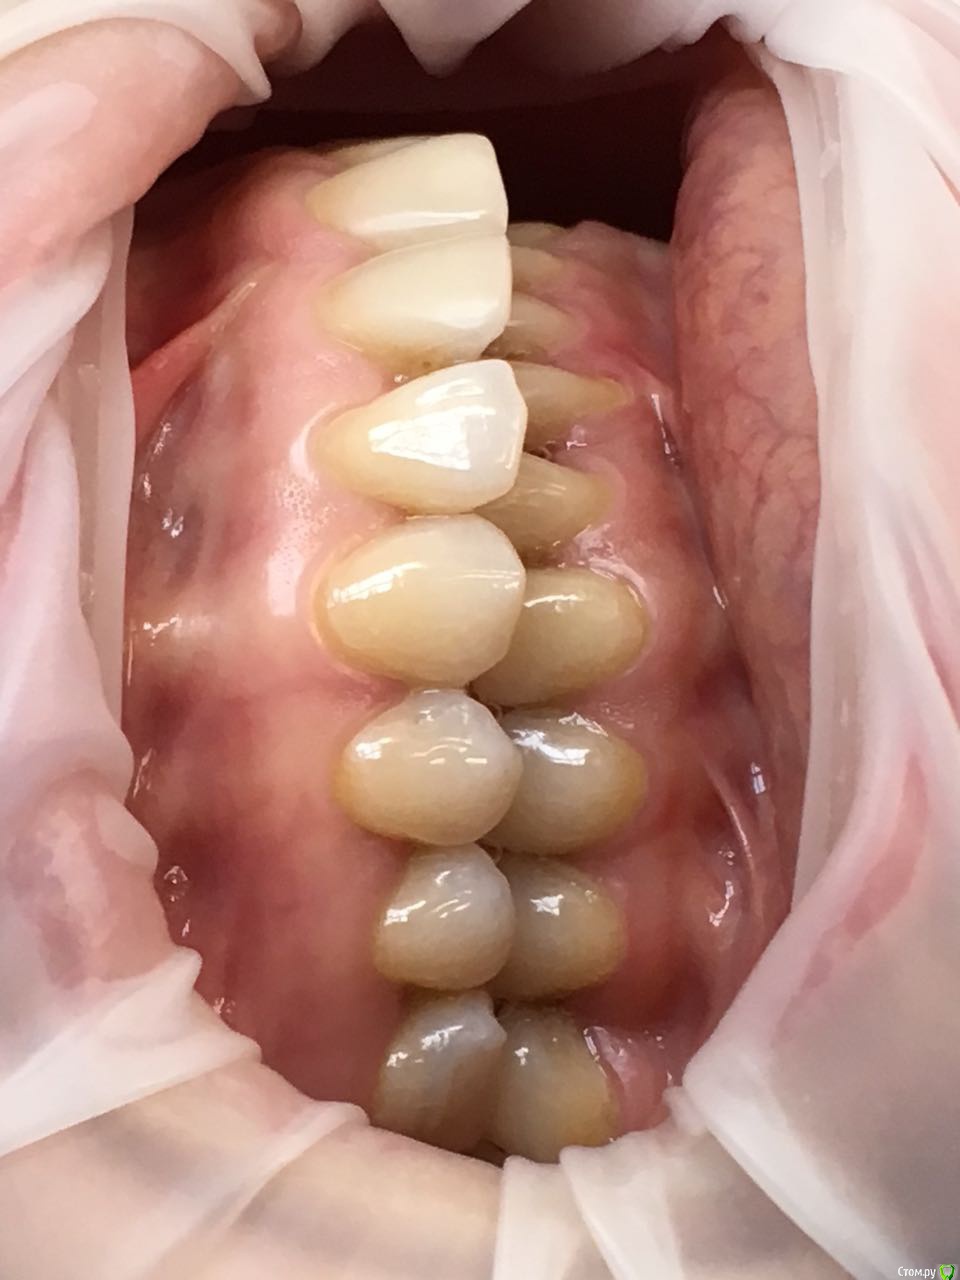

Kema Опубликовано 24 сентября, 2018 Автор Поделиться Опубликовано 24 сентября, 2018 Ещё фото Ссылка на комментарий

Kema Опубликовано 25 сентября, 2018 Автор Поделиться Опубликовано 25 сентября, 2018 У меня нет нижней правой шестёрки. Правая восьмёрка подвинула семёрку, семёрка наклонилась. Левая ретинированная восьмёрка удалена. На правой стороне жевать неудобно. Ещё верхние зубы наклонились вперёд. Начитавшись про ортогнатические операции хотела узнать показана ли мне она. Ссылка на комментарий